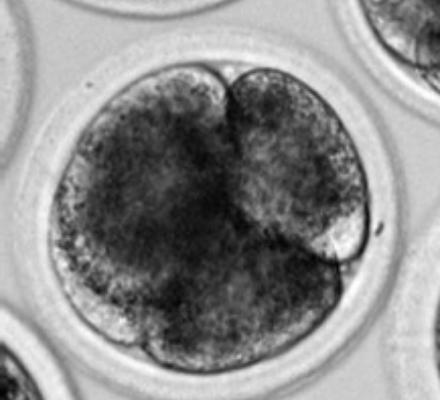

Projevy stárnutí oocytů (vajíček) je možné zvrátit a lze opravit jejich poškození. To, co bylo dosud považováno za biologicky nemožné, dokázal mezinárodní výzkumný tým vedený reprodukční bioložkou Helenou Fulkovou z Ústavu experimentální ...